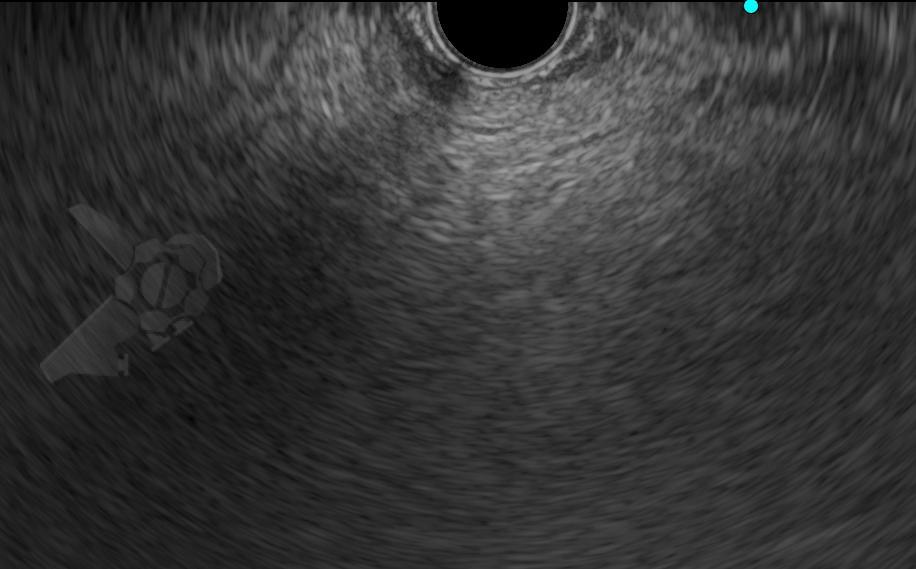

El diagnóstico mediante EUS se basó en la presencia de imágenes pancreáticas hiperecoicas difusas o discontinuas, con bordes poco definidos y dificultad para caracterizar el conducto pancreático principal, en lugar del aspecto habitual bien definido de «sal y pimienta» (véanse las imágenes ilustrativas en el artículo).

Imágenes ilustrativas: